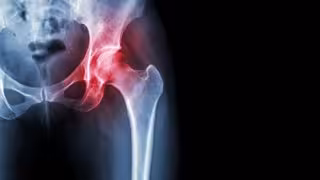

Archivo - Necrosis avascular de cadera

Archivo - Necrosis avascular de cadera - HOSPITAL LA LUZ - Archivo